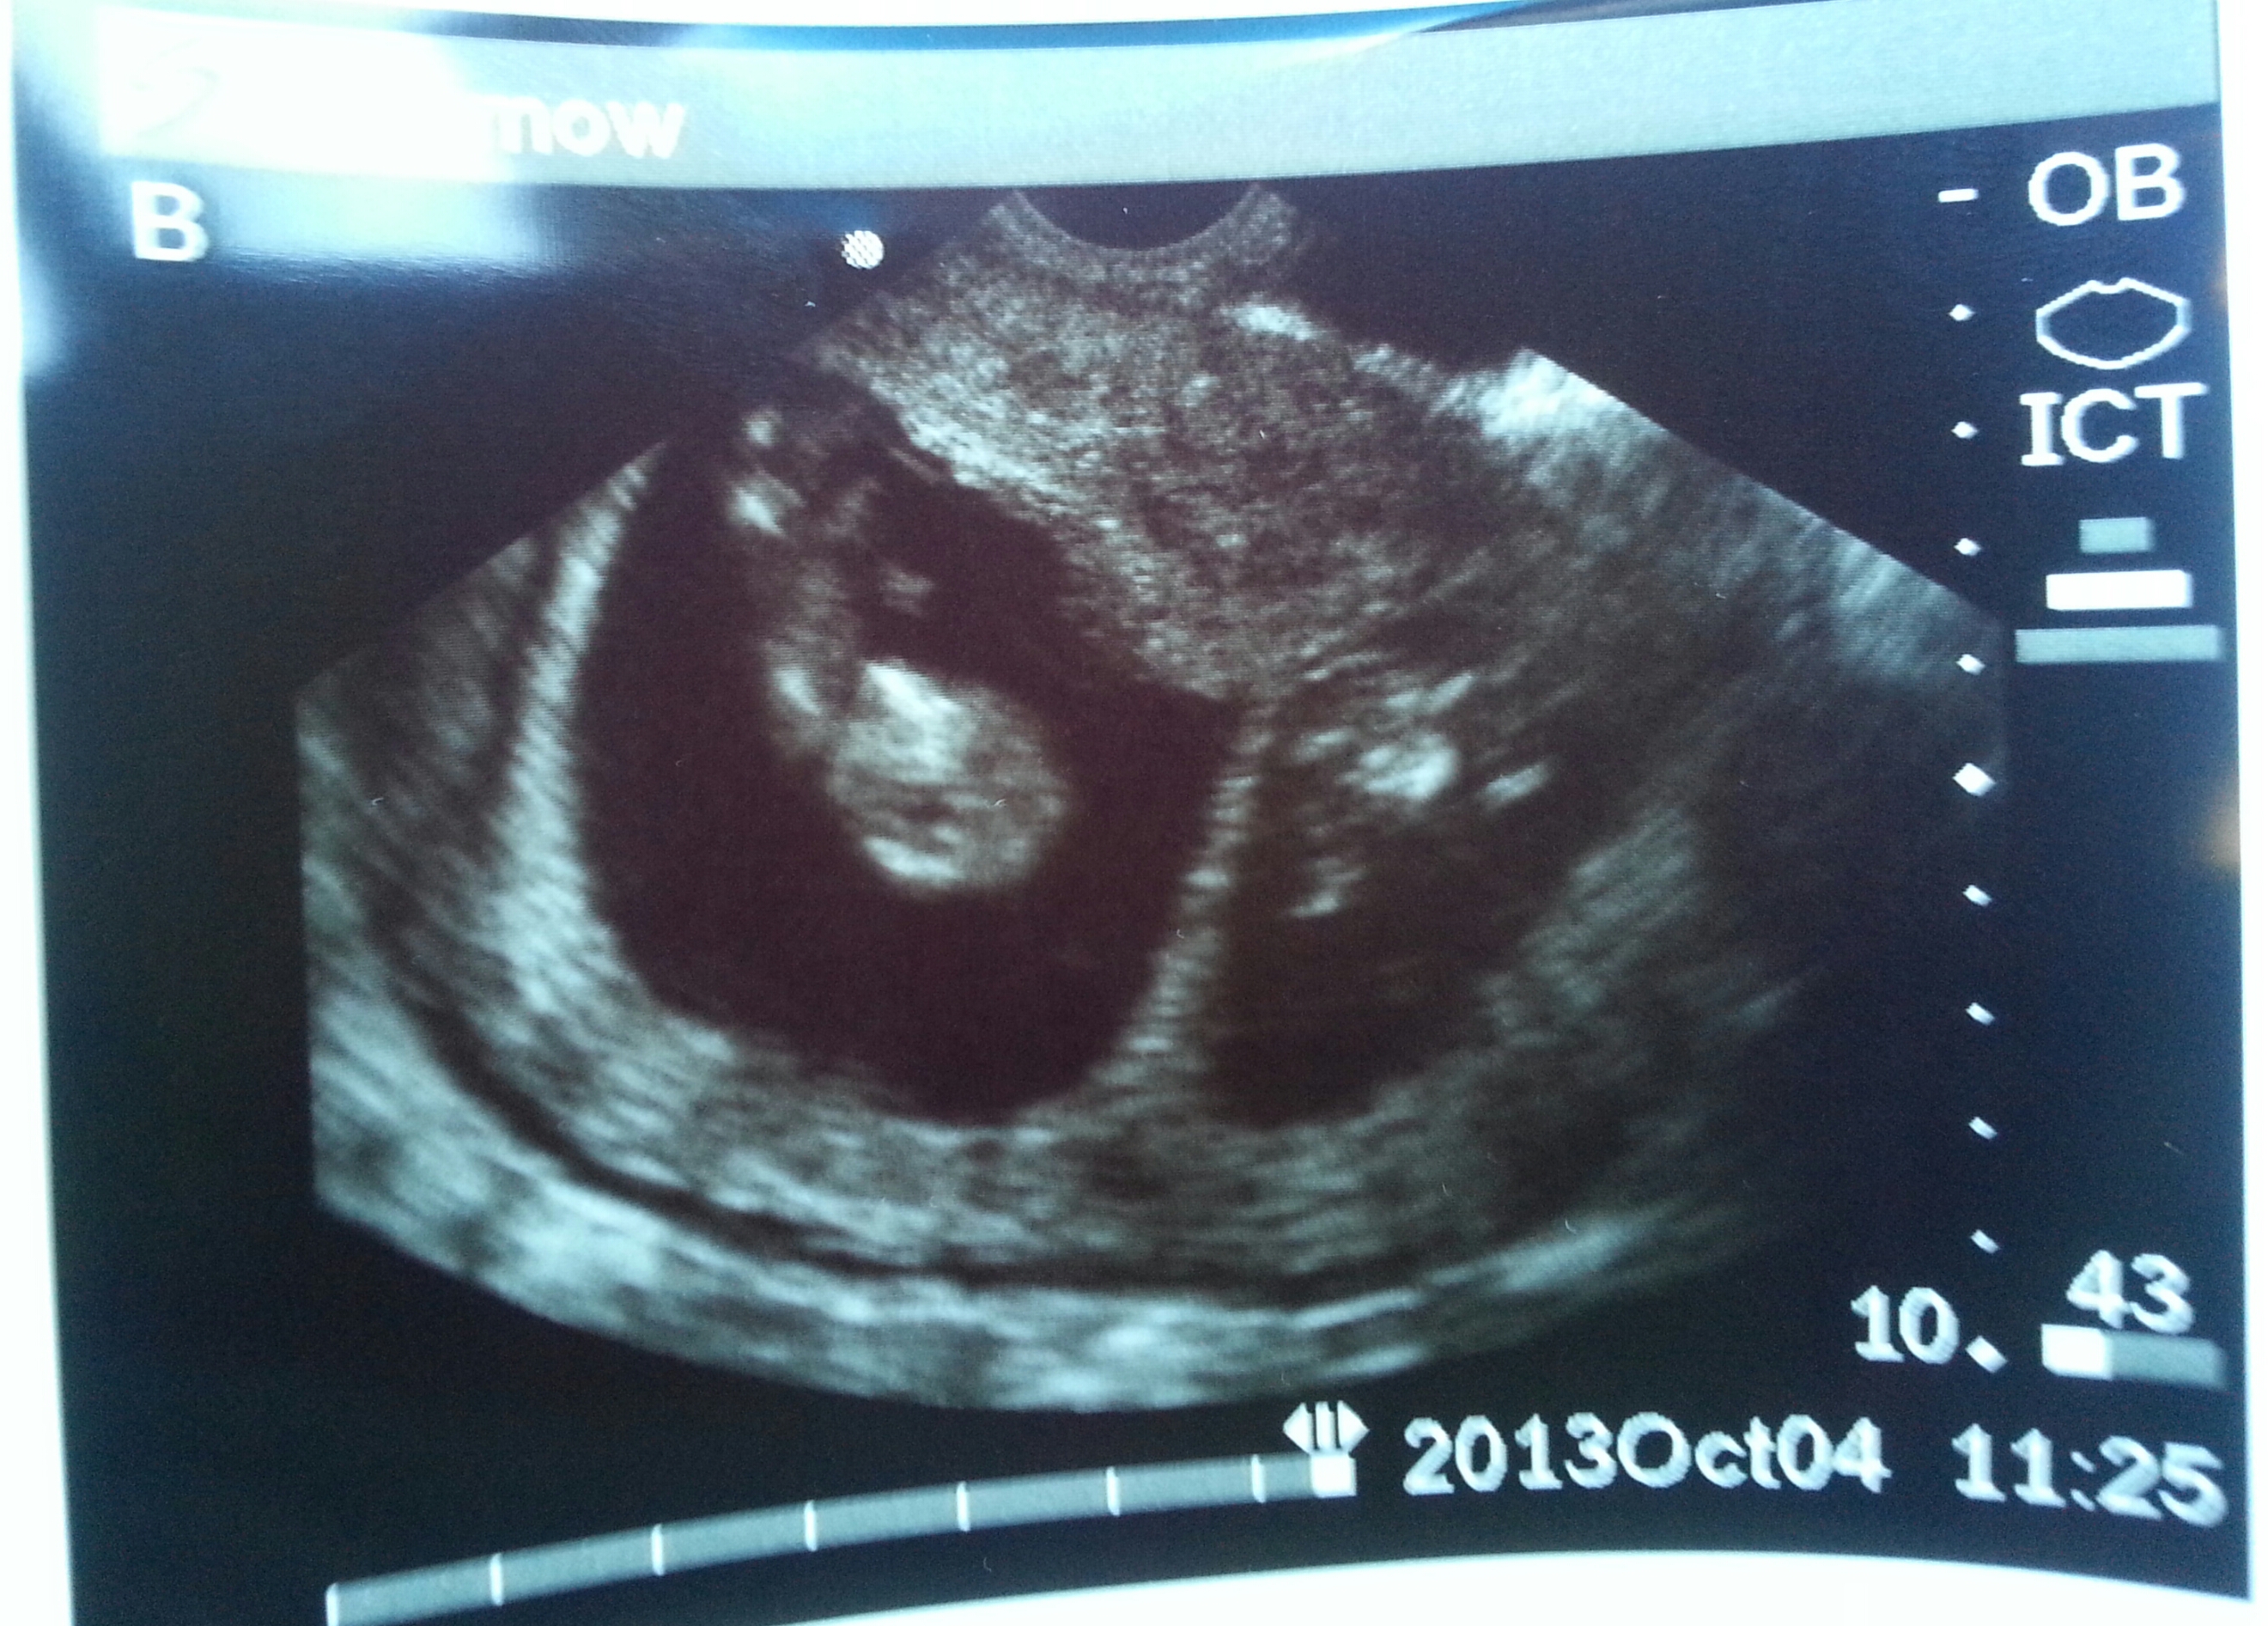

I just had my 11w appointment on Friday (picture below) and they are happy and healthy looking so I decided to officially join your group if you'd have me. Baby A is measuring 2 days behind baby B, but the doctor isn't worried about a thing. A is pictured at an awkward angle so looks much smaller in than B.